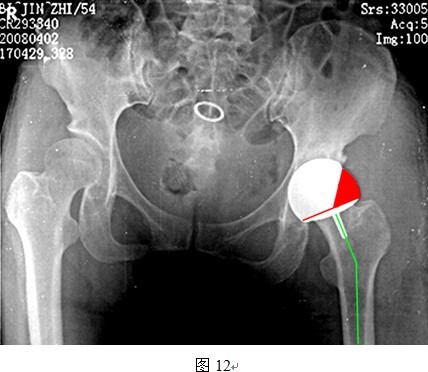

DDH股骨近端的发育异常,颈干角波动幅度较大,在实际应用中,往往无法同时满足上述两个条件。对于合并髋内翻的DDH,即使柄干角较颈干角大5~10度也可能无法达到理想的柄干角(135~140度)。同样,对于颈干角本身就大于140度的患者,若坚持将柄干角再加大10度,则使得柄干角过大,头臼假体包容率减少,造成应力集中,磨损增加(图12所示即为大柄干角与头臼小包容率的关系)。因此,颈干角过大或者过小的DDH患者均不是THRA良好适应症,需要严格筛选。